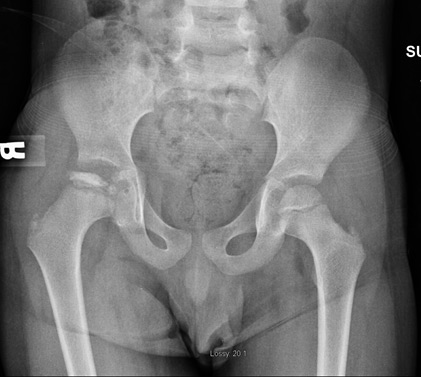

10. Kids - hip joint referral

ALWAYS sceen an adolescents hip (quick FADDIR) if they have knee pain 👃

Refers medially usually

eg Perthes (5-10), SUFE (10+)